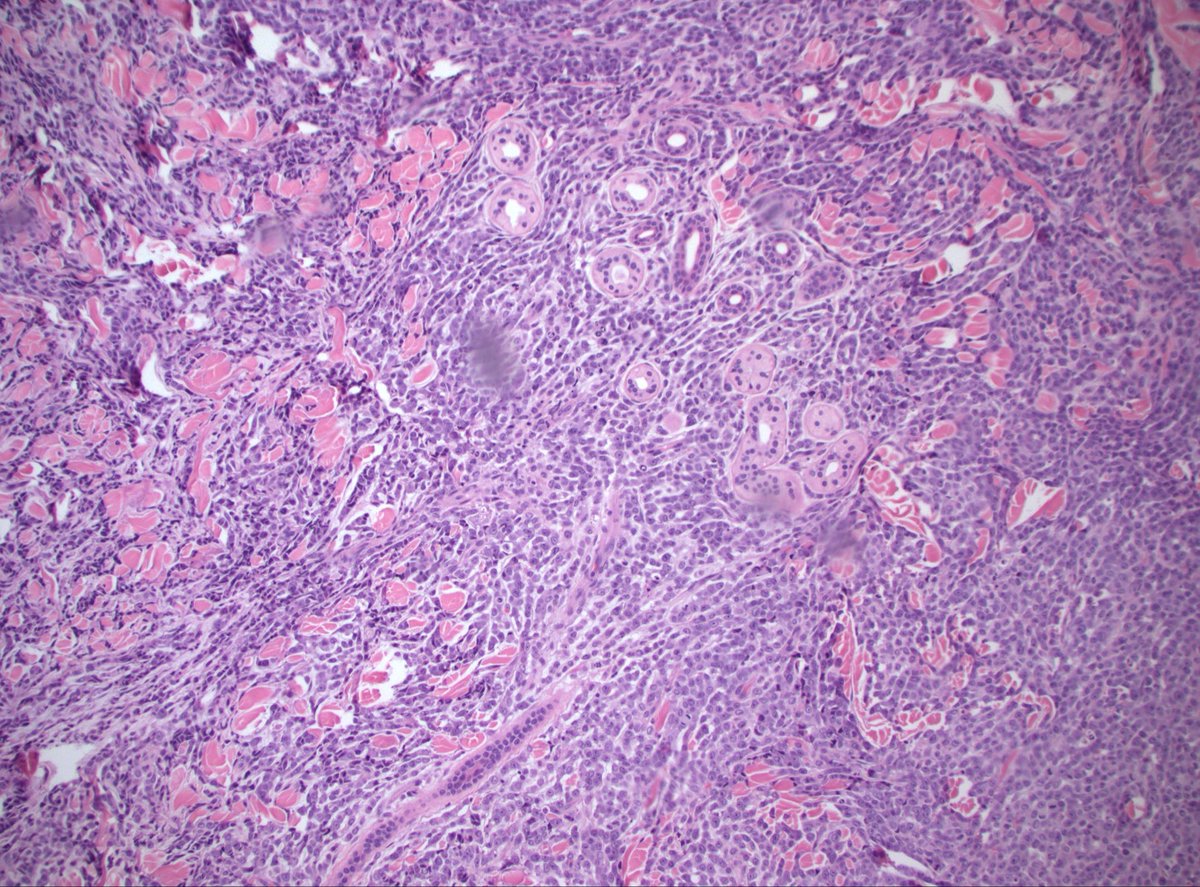

🔔 Answer Reveal! This myxoid mystery 🪼🔬 was… 🥁 Matrix-producing metaplastic carcinoma! 💥🦴 CAM5.2 shown below 👇. Note the markedly atypical focus with glandular differentiation and abruption transition to chondroid 👀 #PathQuiz #PathX #PathTwitter #breastpath